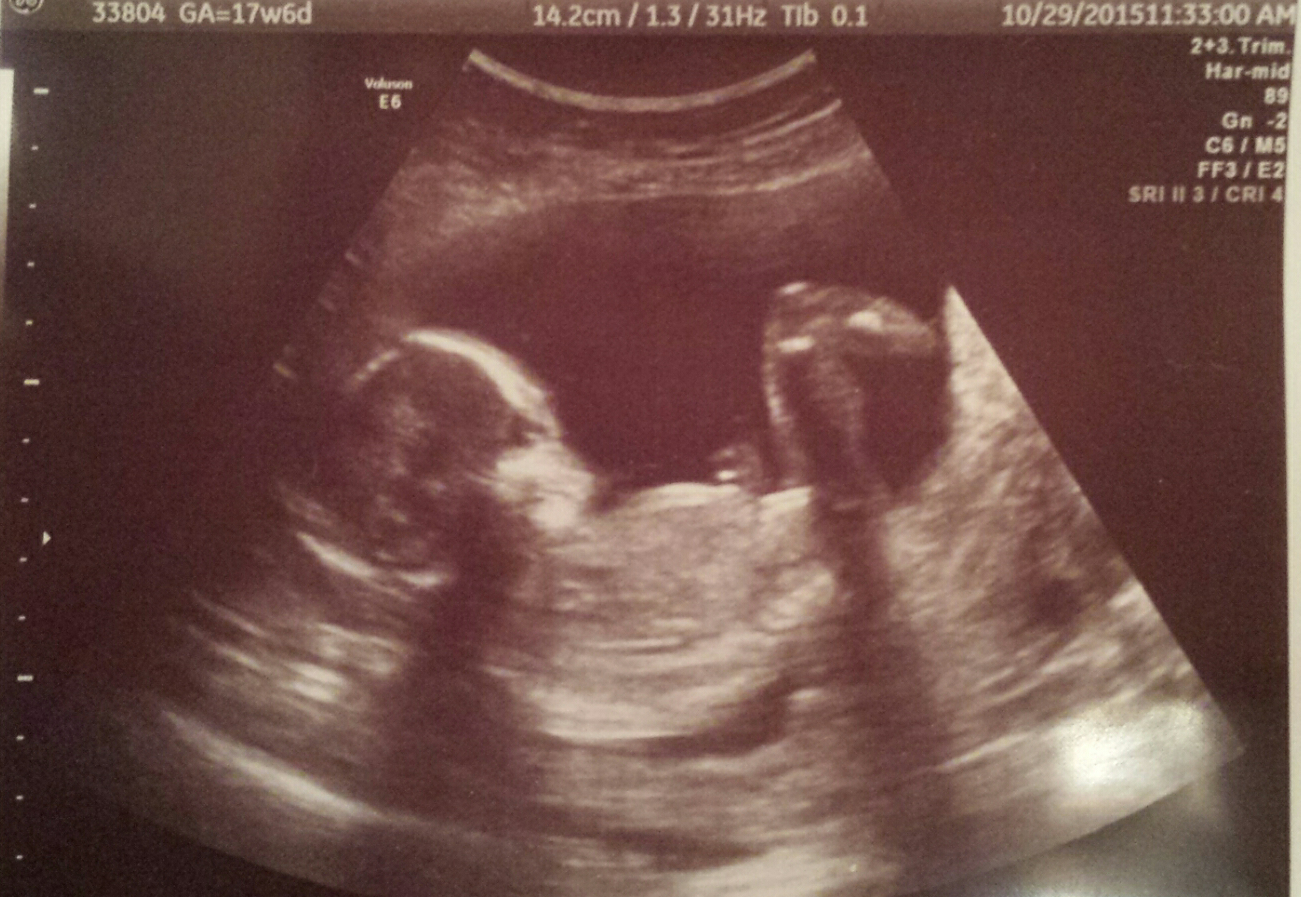

15w2d -- little boy is camera shy! He's laying with his arm curled under his face. His face resembles a Halloween mask! Lol super active with a heartbeat going from 144-151. Stretched out with his feet on one side, and head on the other.